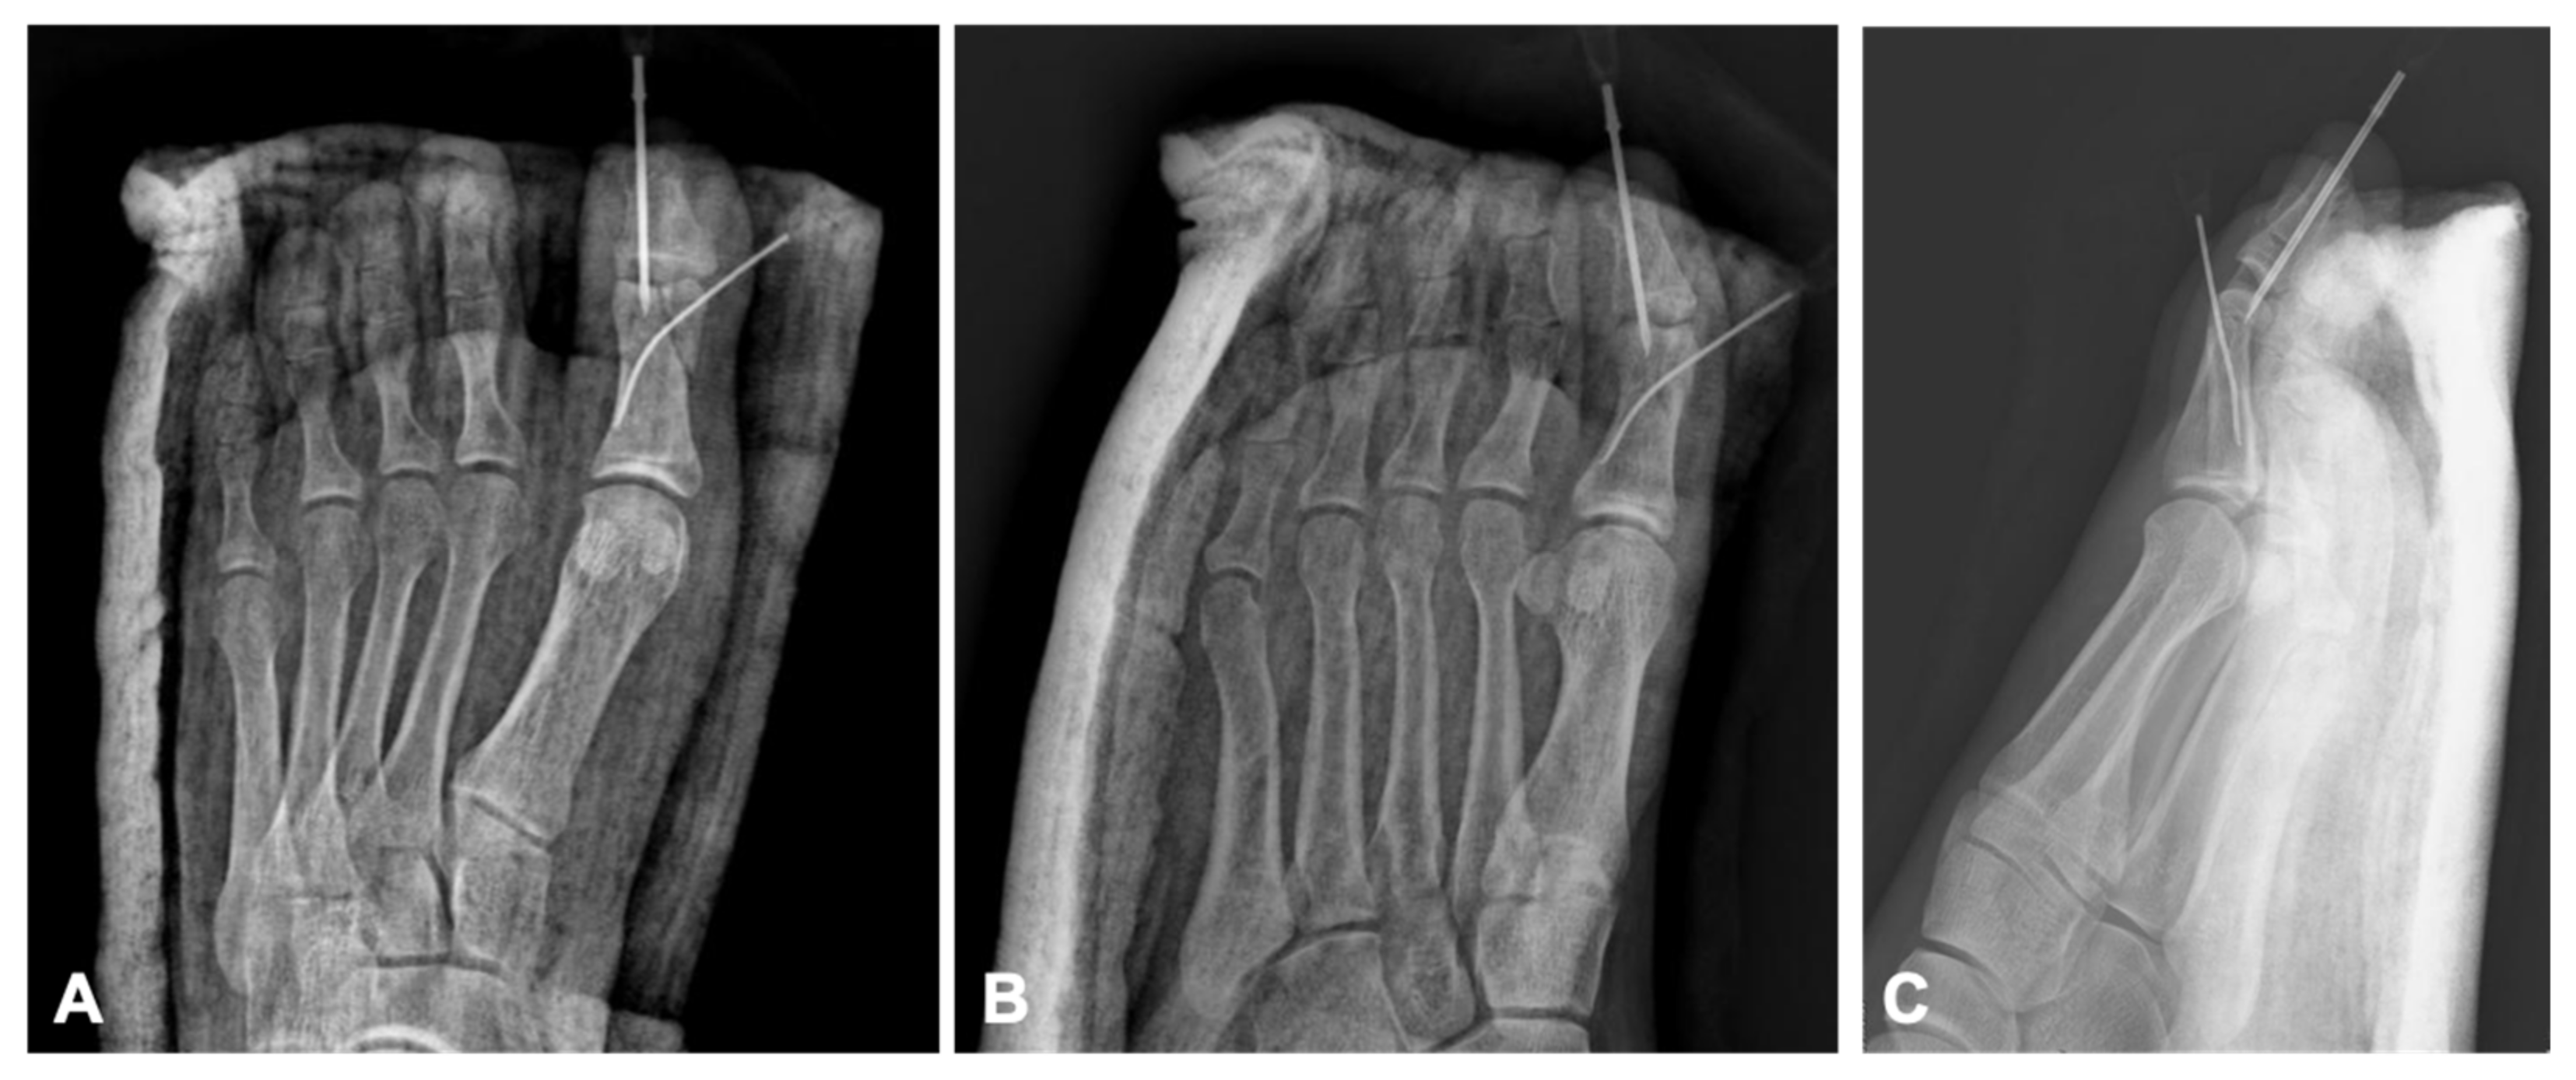

Figure 2). The patient was discharged and scheduled for weekly follow-ups after prescription of amoxicillin clavulanic acid 1 g twice a day. The hypodermic needles were removed during the fourth week in the outpatient clinic and passive range of motion exercises and weight bearing were begun gradually. After 6 weeks, radiographs showed fracture union (

Figure 3), and the patient resumed normal walking and weight bearing with no pain. Control radiographs were also obtained in the third month showing fracture healing (